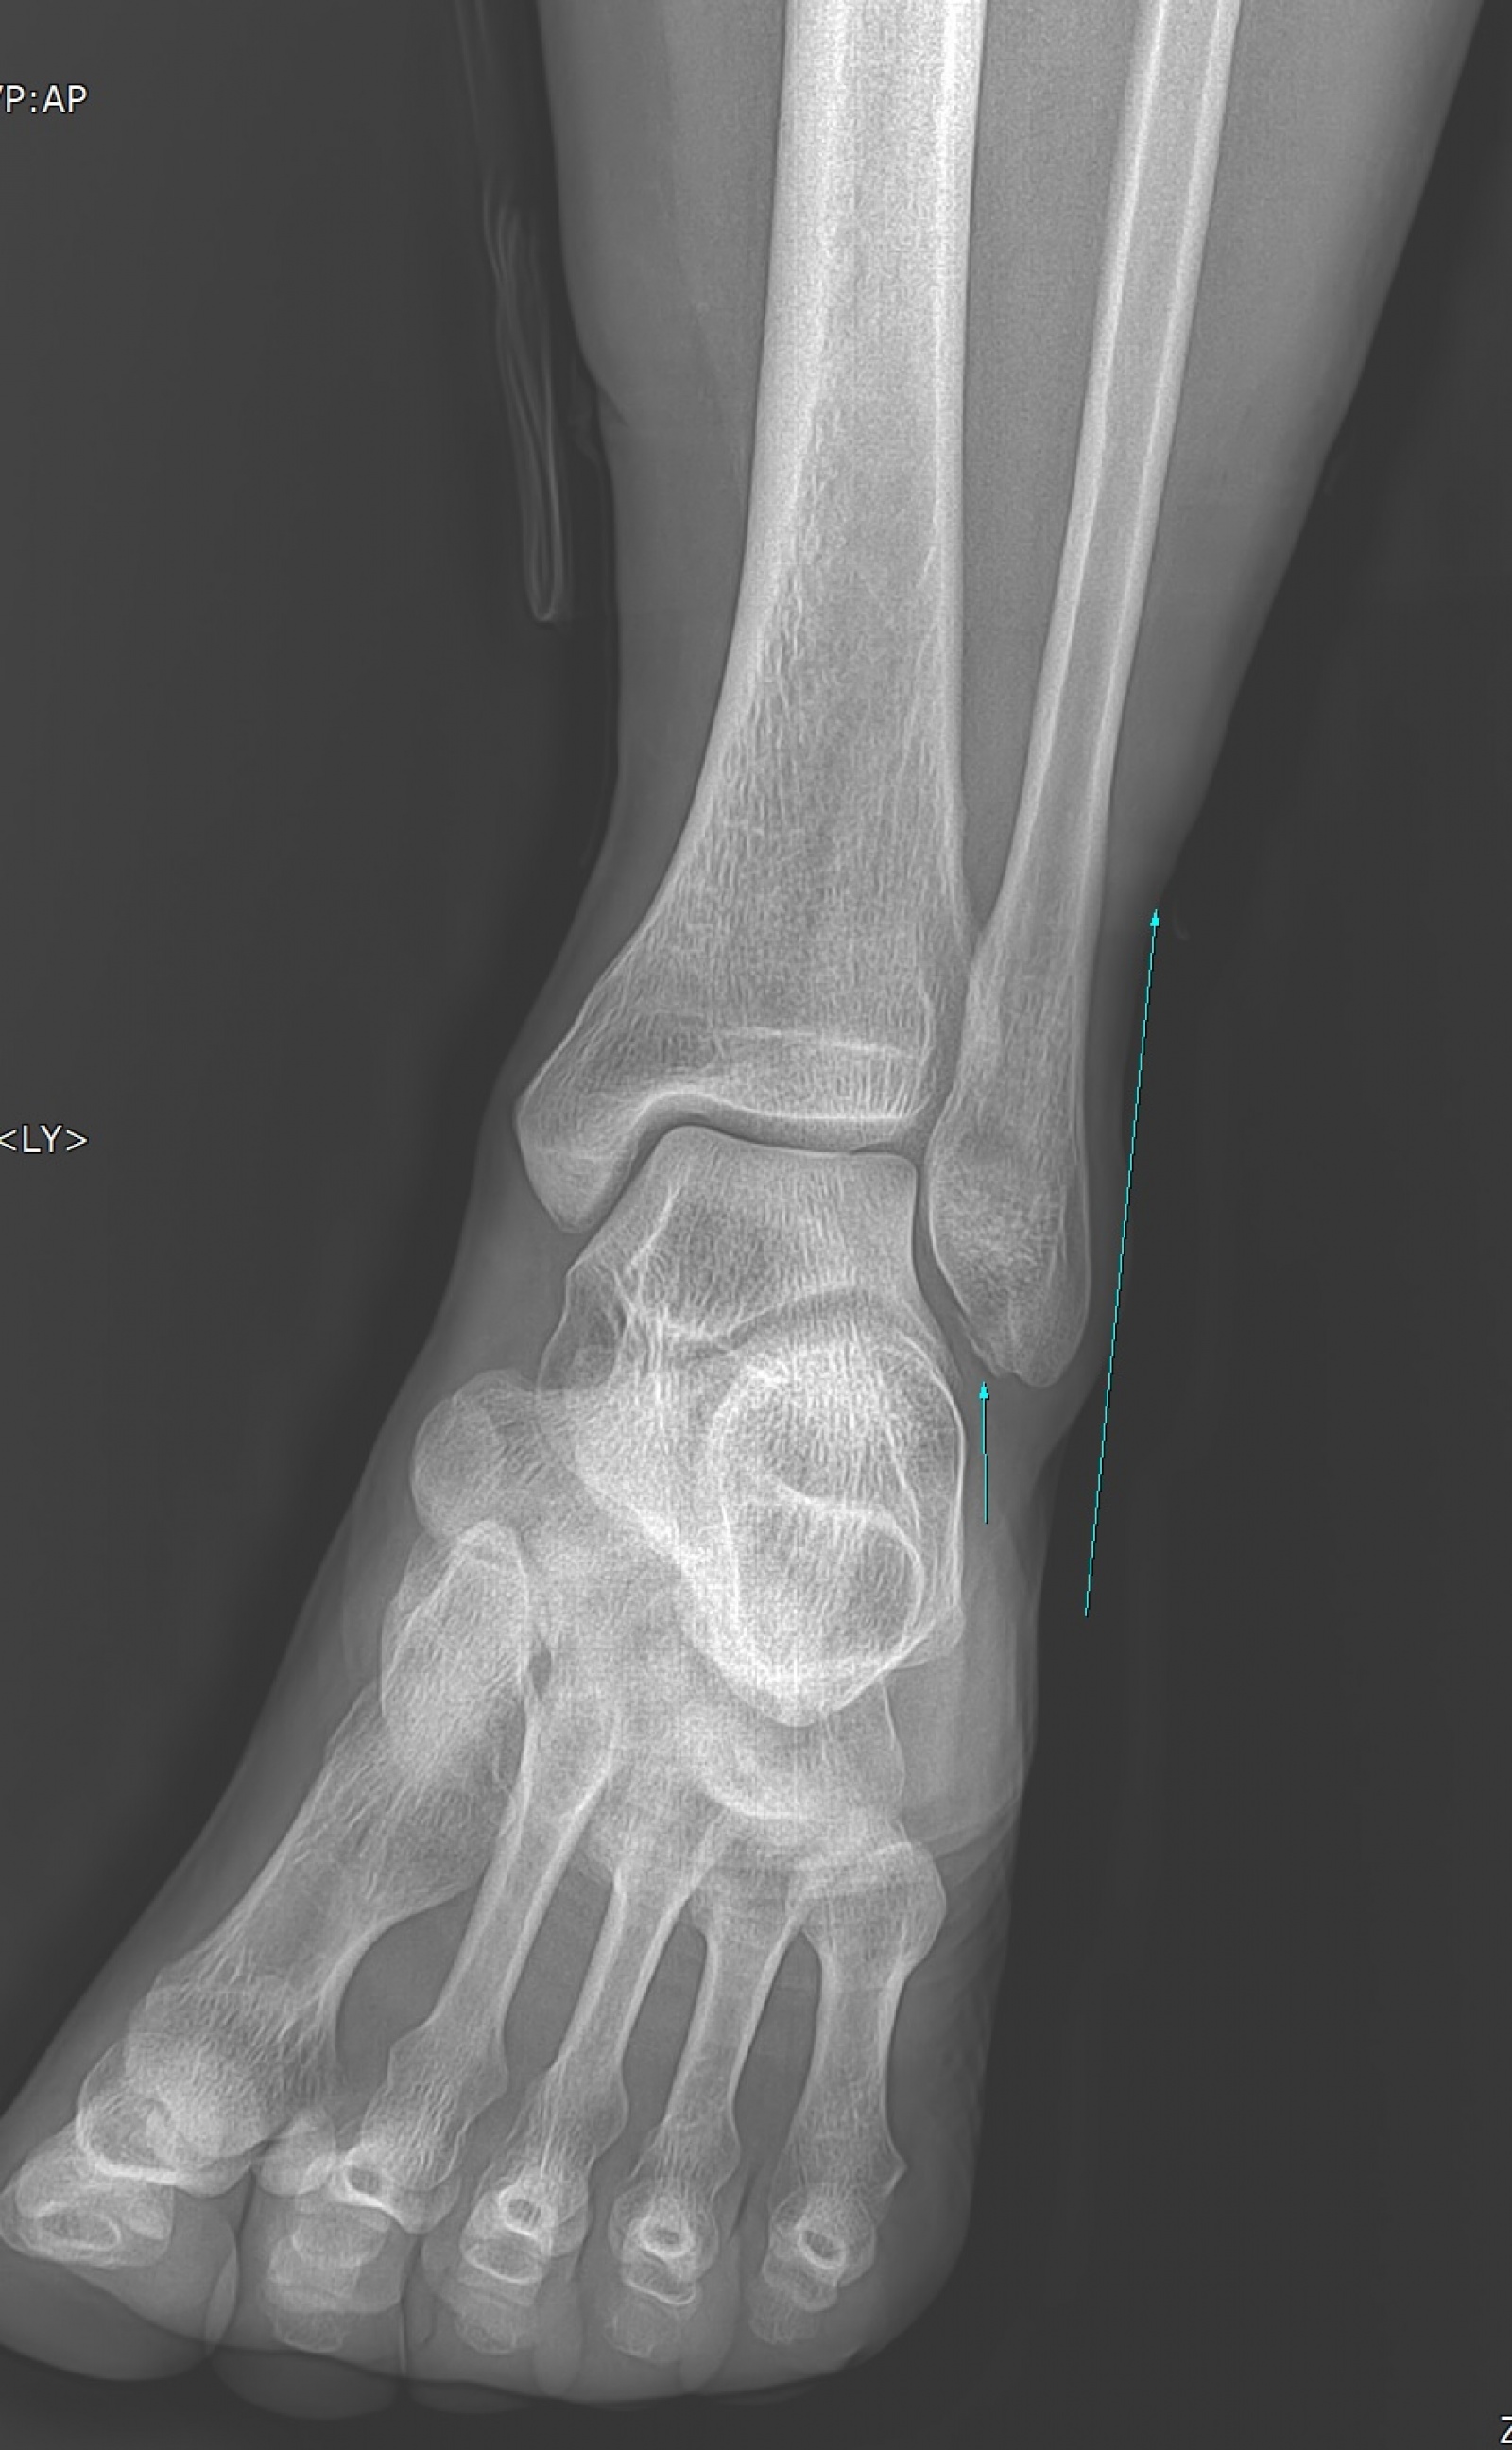

작년인가 재작년인가 하비페어 직전에 맹장염 수술받느라고 작품을 못냈던 적이 있는데 이번에는 직장계단에서 술러서 발목이 골절되었네요.

이번 골절은 어제 살짝 붕대 풀어봤더니 다리가 너무 부어서 도저히 갈 용기가 안나네요.^^;